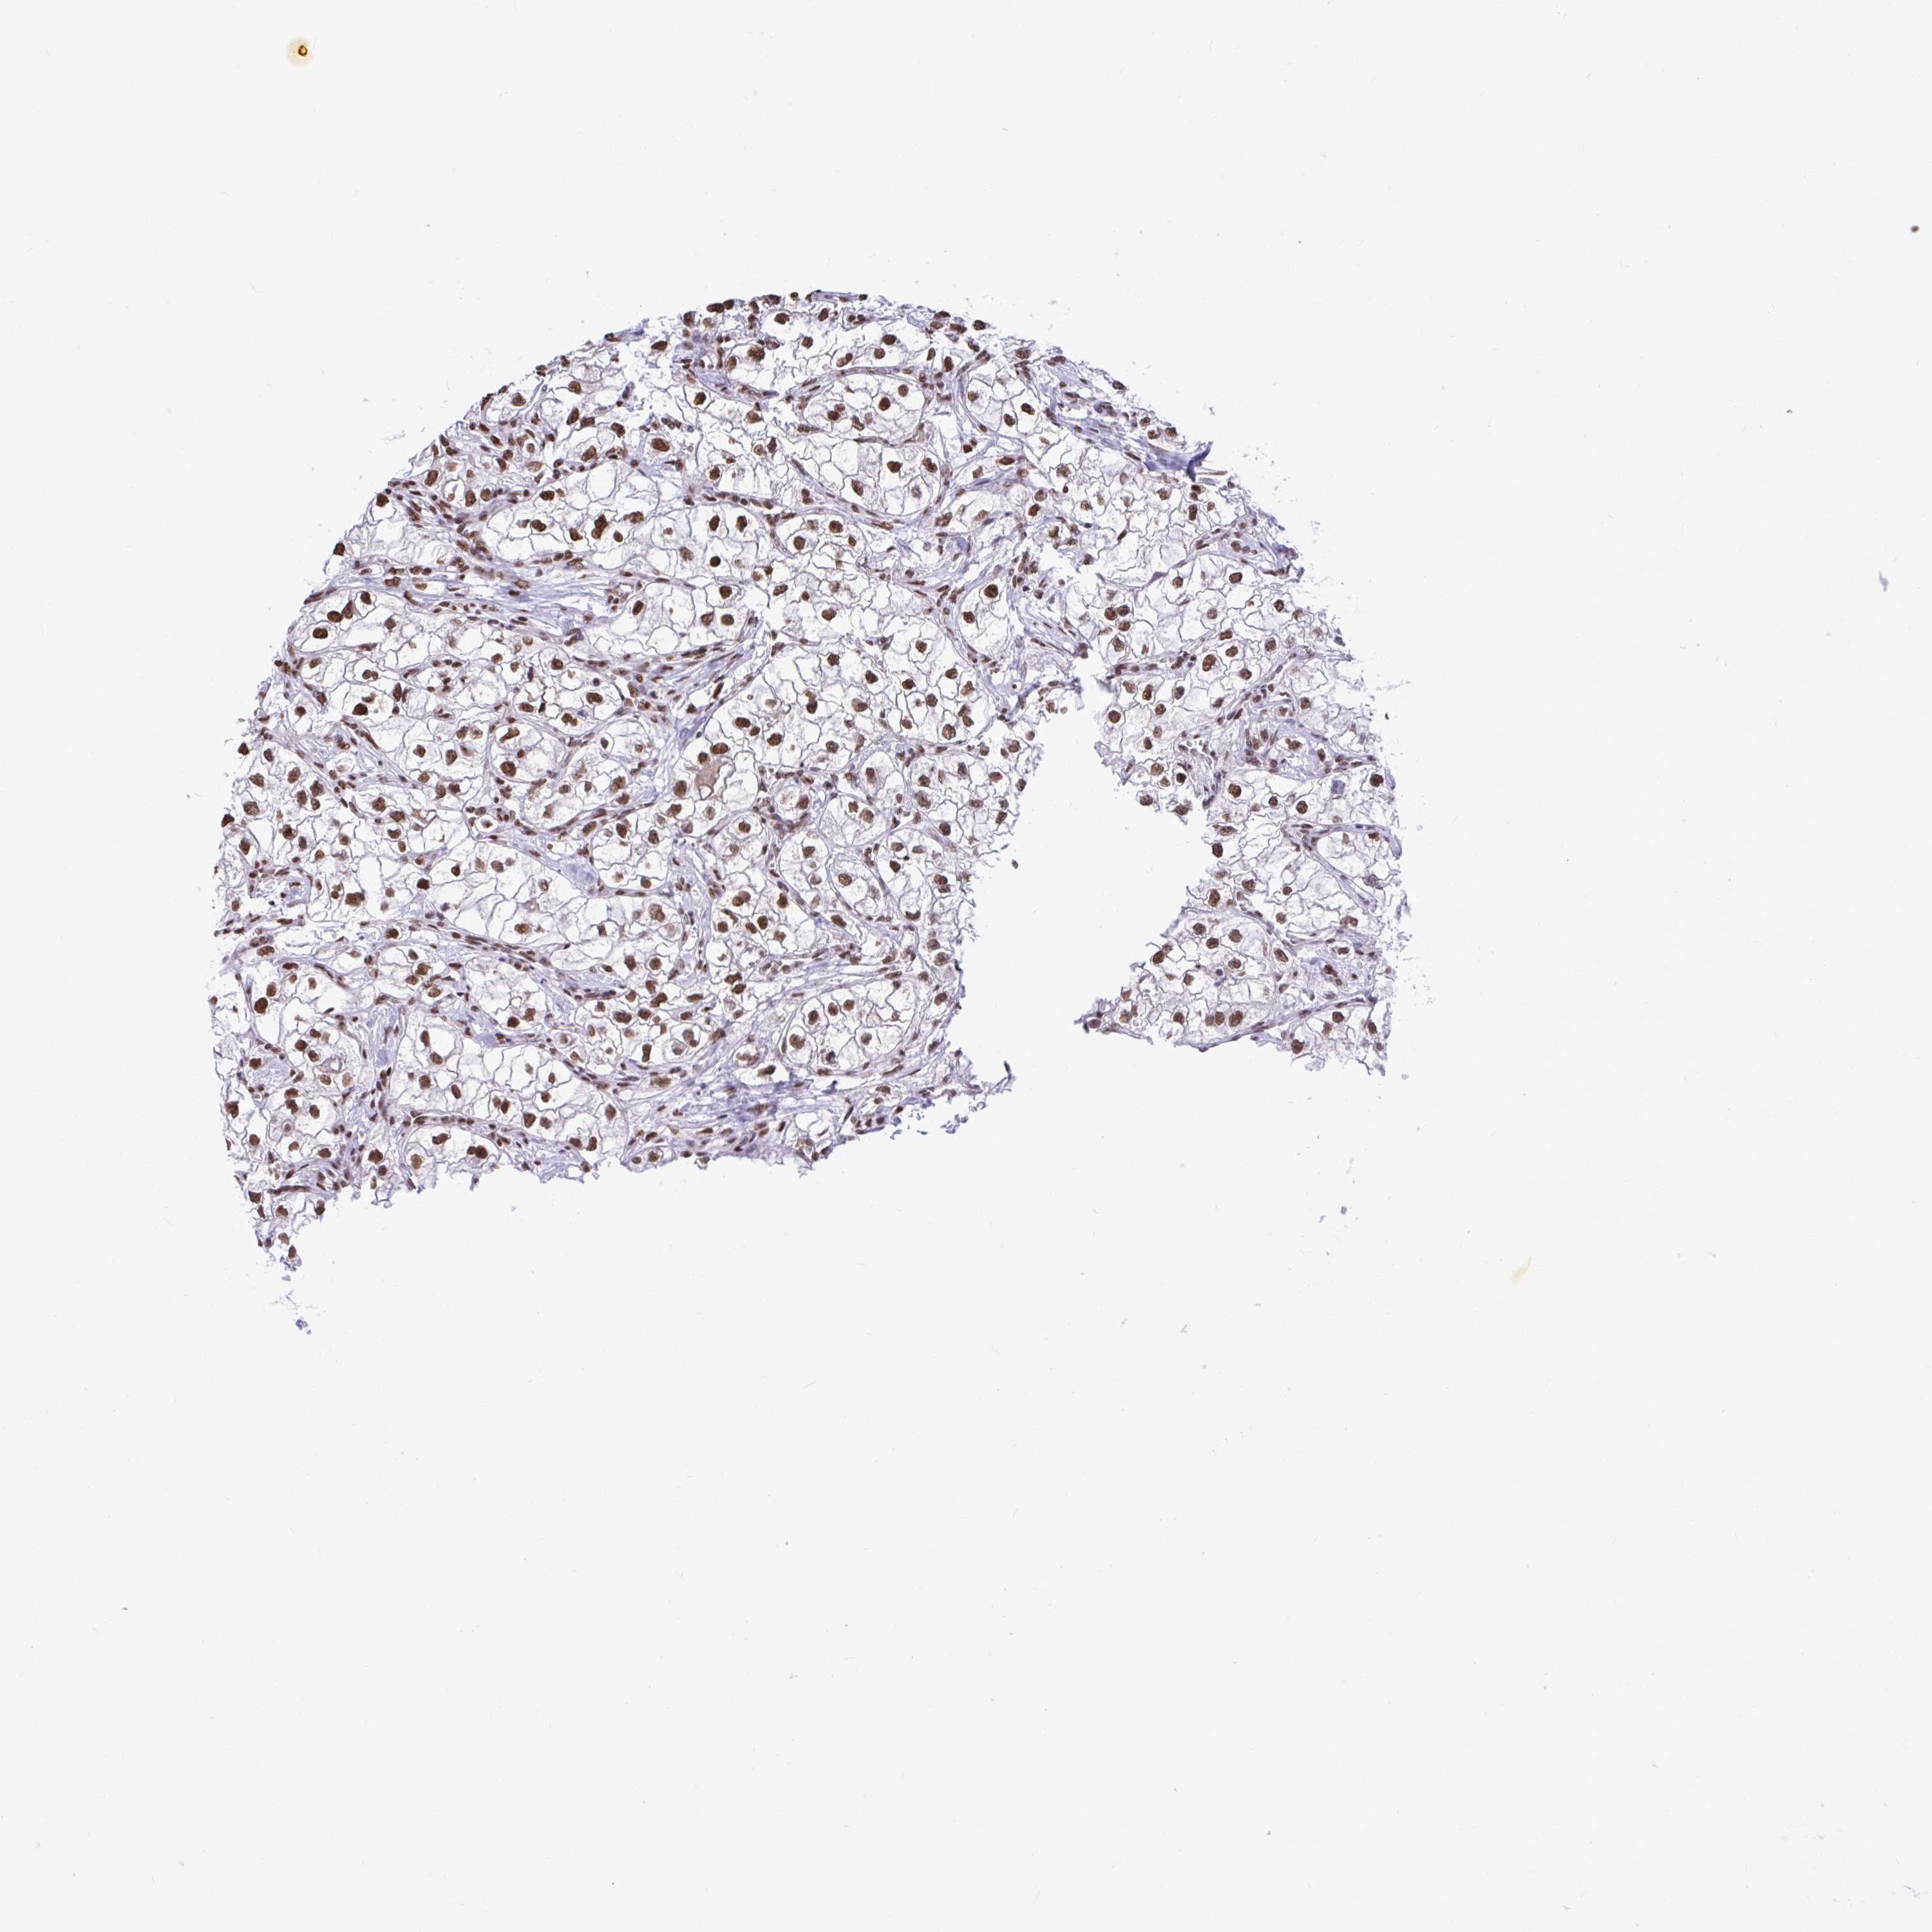

KIDNEY CHROMOPHOBE (TCGA) - Interactive survival scatter ploti

The Survival Scatter plot shows the clinical status (i.e. dead or alive) for all individuals in the patient cohort, based on the same data that underlies the corresponding Kaplan-Meier plots. Patients that are alive at last time for follow-up are shown in blue and patients who have died during the study are shown in red.

The x-axis shows the expression levels (FPKM) of the investigated gene in the tumor tissue at the time of diagnosis. The y-axis shows the follow-up time after diagnosis (years). Both axes are complimented with kernel density curves demonstrating the data density over the axes. The top density plot shows the expression levels (FPKM) distribution among dead (red) and alive patients (blue). The right density plot shows the data density of the survived years of dead patients with high and low expression levels respectively, stratified using the cutoff indicated by the vertical dashed line through the Survival Scatter plot. This cutoff is automatically defined based on the FPKM cutoff that minimizes the p-score. The cutoff can be changed by dragging the vertical line or by entering a cutoff value in the square labeled "Current cut-off".

Under the Survival Scatter plot the p-score landscape (black curve; left axis) is shown together with dead median separation (red curve; right axis). Dead median separation is the difference in median mRNA expression between patients who have died with high and low expression, respectively. It is calculated as follows: median FPKM expression of dead patients with high expression - median FPKM expression of dead patients with low expression. This is intended to aid the user in visually exploring custom cutoffs and the associated p-scores and dead median separation.

Individual patient data is displayed and can be filtered by clicking on one or more of the category buttons on the top of the page. Categories describing expression level and patient information include: high, low, alive, dead, female, male and tumor stages. The scale of the x-axis can be toggled between linear and log-scale by clicking on the "x log" button. Mouse-over function shows TCGA ID, patient information and mRNA expression (FPKM) for each patient.

& Survival analysisi

Kaplan-Meier plots summarize results from analysis of correlation between mRNA expression level and patient survival. Patients were divided based on level of expression into one of the two groups "low" (under cut off) or "high" (over cut off). X-axis shows time for survival (years) and y-axis shows the probability of survival, where 1.0 corresponds to 100 percent.

HNRNPDL is not prognostic in Kidney Chromophobe (TCGA)

Best expression cut offi

Based on the FPKM value of each gene, patients were classified into two groups and association between prognosis (survival) and gene expression (FPKM) was examined. The best expression cut-off refers the FPKM value that yields maximal difference with regard to survival between the two groups at the lowest log-rank P-value. Best expression cut-off was selected based on survival analysis .

When clicking on this number, the vertical dashed line indicating cut-off, the interactive survival plot, and the Kaplan-Meier curve will be adjusted to show results based on the best expression cut-off.

: 99.24

Median expressioni

Median expression refers to the median FPKM value calculated based on the gene expression (FPKM) data from all patients in this dataset. When clicking on this number, the vertical dashed line indicating cut-off, the interactive survival plot, and the Kaplan-Meier curve will be adjusted to show results based on the median expression.

: N/A

Median follow up timei

Median follow up time refers to the median time (years) after diagnosis with this type of cancer, based on clinical data from all patients in this dataset.

P scorei

Log-rank P value for Kaplan-Meier plot showing results from analysis of correlation between mRNA expression level and patient survival.

N/A

5-year survival highi

5-year survival for patients with higher expression than the expression cutoff.

For melanoma and glioma, 3-year survival is shown.

5-year survival lowi

5-year survival for patients with lower expression than the expression cutoff.

TCGA RNA samplesi

RNA-seq data is reported as average FPKM (number Fragments Per Kilobase of exon per Million reads), generated by the The Cancer Genome Atlas (TCGA) .

Normal distribution across the dataset is visualized with box plots, shown as median and 25th and 75th percentiles. Points are displayed as outliers if they are above or below 1.5 times the interquartile range. FPKM values of the individual samples are presented next to the box plot.

Average pTPM 90.4

Number of samples 64